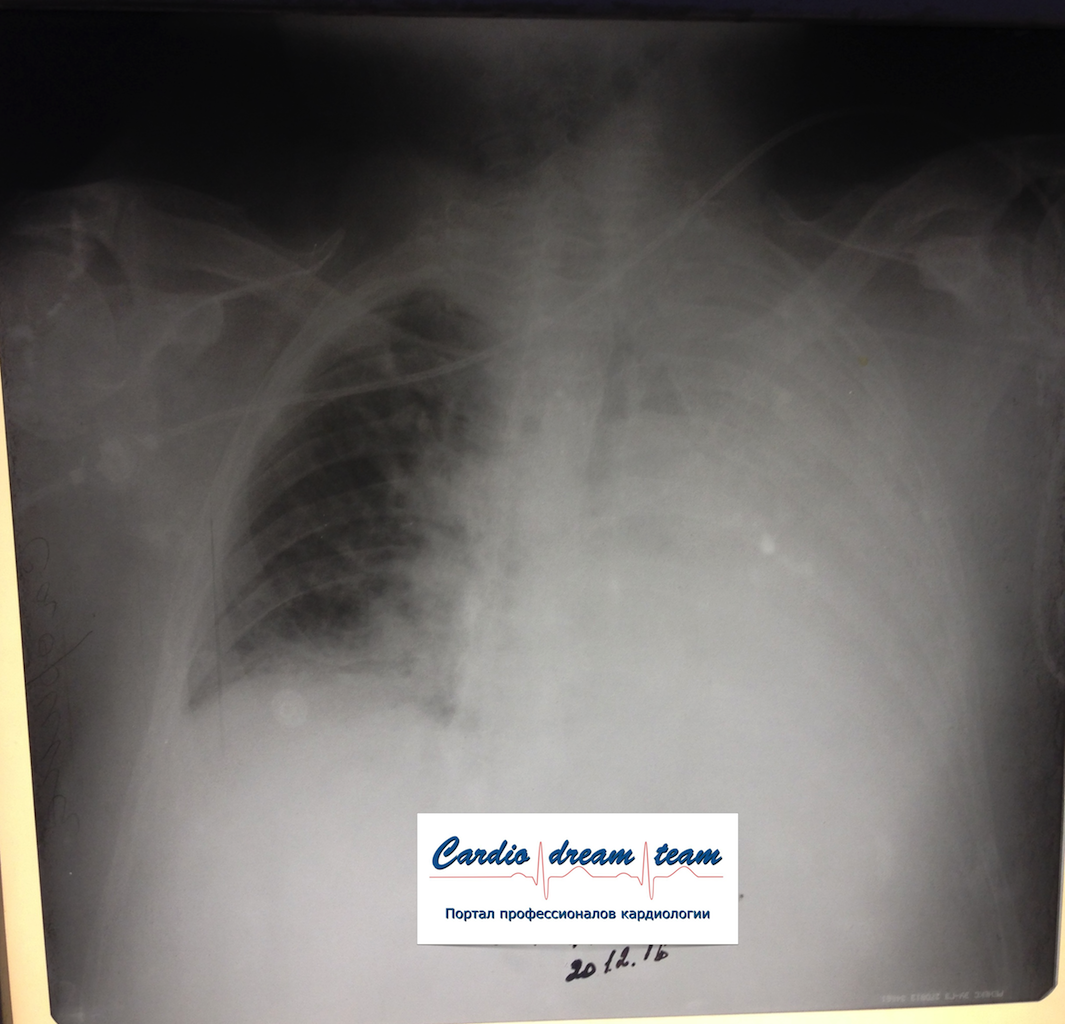

Ателектаз слева. Гнойный эндобронхит с закупоркой бронхов гноем.

Обсуждалось в Госпитале Ослабленных Сердец